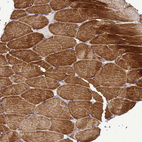

Immunohistochemical staining of human skeletal muscle shows strong cytoplasmic positivity in myocytes.